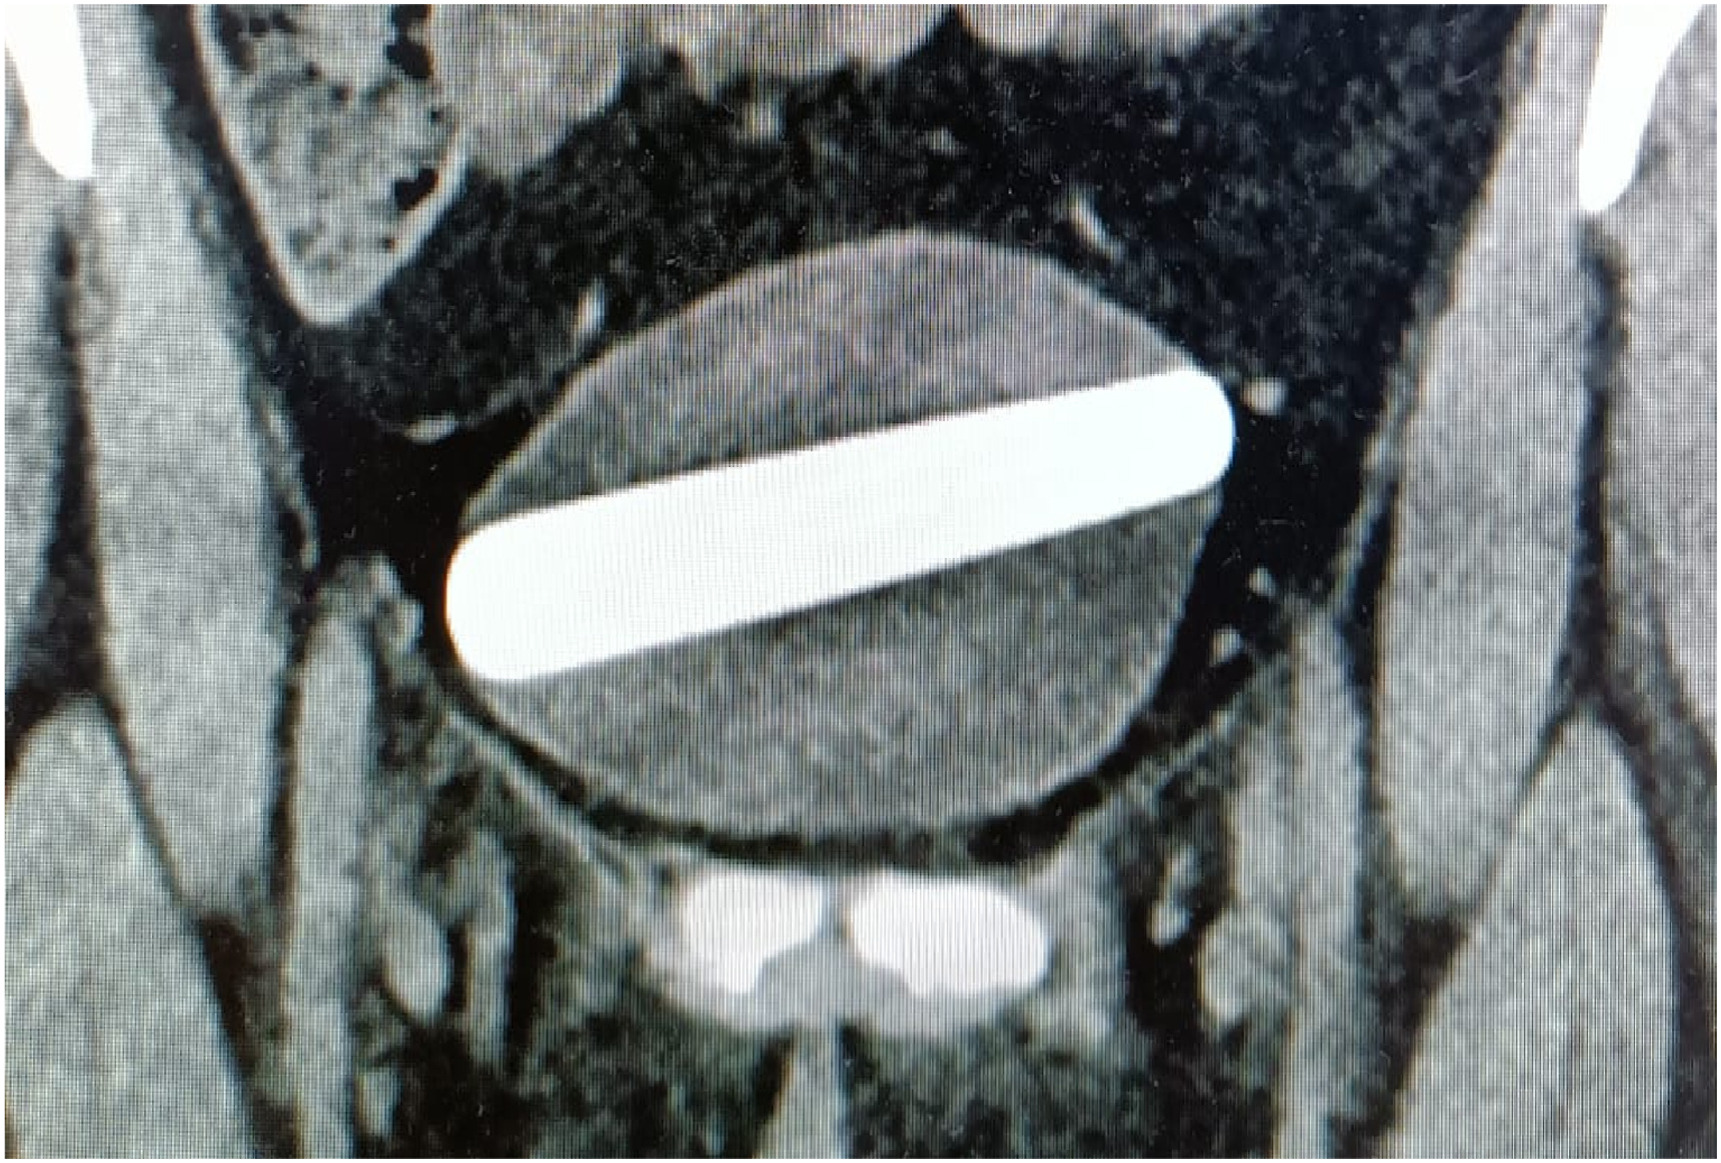

De læger på Shaare Zedek Medical Center i Jerusalem, der behandlede kvinden, mener, at det er den bredeste genstand, der er fjernet fra blæren, da den målte 10 cm i længden og 2,5 cm i bredden.

De startede med at foretage en ultralydsscanning og tage røntgenbilleder af kvinden, som viste, at objektet sad fast inde i hendes blære.